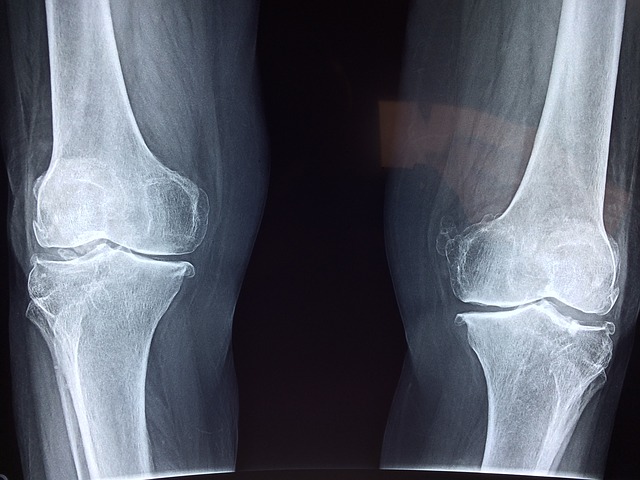

Рентгенологическое исследование: Рентгеновские снимки предназначены, прежде всего, для исключения сопутствующих повреждений кости и выполняются при любой травме коленного сустава. Сами связки на рентгеновских снимках не просматриваются.